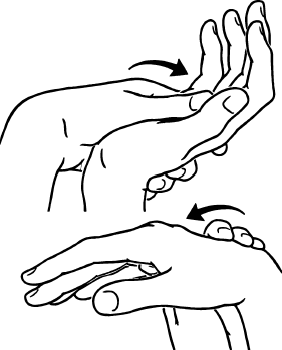

(2) 수동운동검사

- 손목 수동 굴곡, 신전, 회외, 회내검사를 합니다.